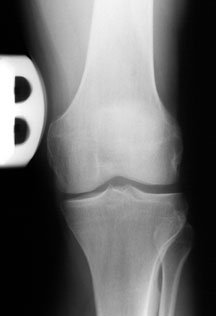

As you will learn, deficiency of the PLC causes an abnormal increase in the amount of joint space between the femur and tibia on the lateral (outer) part of the knee. This is termed abnormal lateral joint opening – and this places harmful forces on a healing ACL or PCL graft that eventually causes the graft to fail.

This is clearly evident in the x-ray on the left as shown by the yellow arrow – compared to the normal, uninjured knee on the right. [The white things are the metal fixations put in during the operation.]